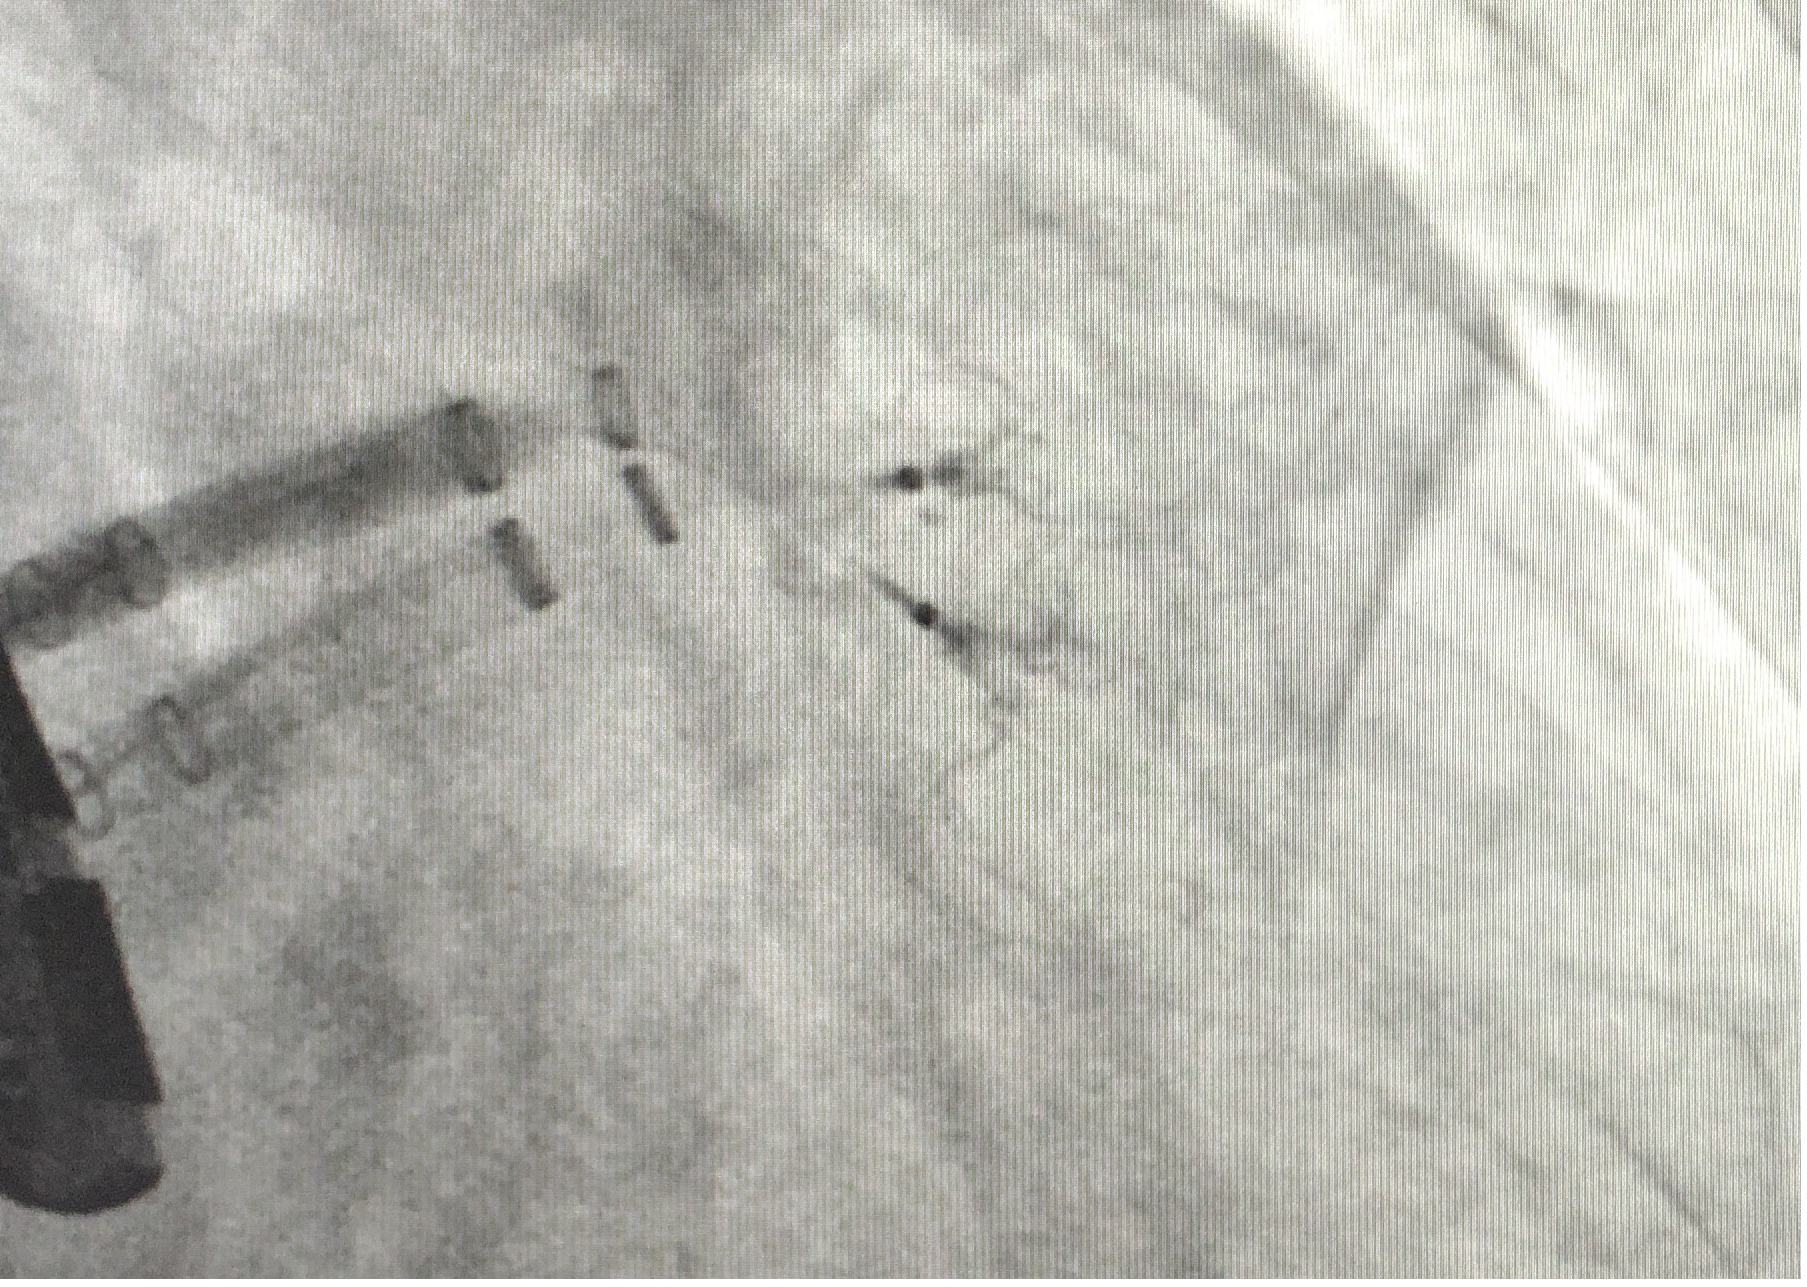

患者为66岁男性,永久性房颤5年余。既往有脑卒中史,高血压病史。间断口服华法林治疗,期间有多个器官及部位出血。入院房颤相关评分:CHA2DS2-VASc评分5分,HAS-BLED出血评分4分。经科室讨论行左心耳封堵术以减低脑卒中和出血风险。术中造影见巨大开口“菜花状”左心耳,经仔细分析病例特点为巨大开口(直径为37mm),且有两个较大的分叶。无法用最大型号WATCHMAN 封堵器(直径为33mm)封堵成功。遂改变封堵策略,选择使用两枚封堵伞,植入两个分叶分别进行封堵,即左心耳封堵的Kissing封堵技术。术中选用两枚封堵器(直径为24mm)送入两个分叶,进行Kissing封堵,封堵效果很完美。